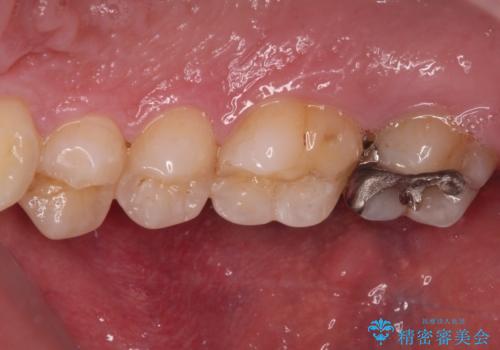

- 近医にて、銀歯の周りの歯が欠けてむし歯のようになっていると言われたとのことで来院された患者様です。

非常に咬合力が強く、銀歯やセラミックのような堅い素材では歯にダメージがかかり、治療を繰り返す可能性が高いと思われたので、ゴールドインレー(白金加金インレー、PGAインレー)にて、治療中の歯と銀歯が装着されている歯を修復治療することとしました。